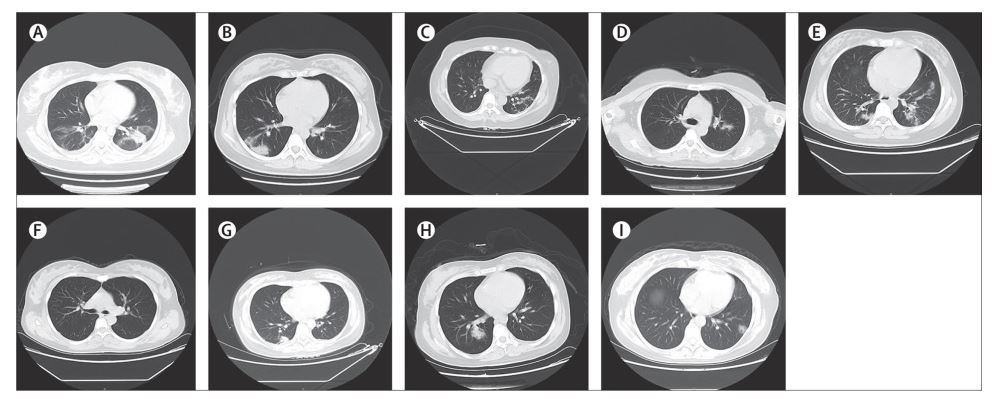

FigureChest CT scans (transverse plane) of nine patients

(A) Patient 1: left-sided patchy consolidation and multiple bilateral ground-glass opacities. (B) Patient 2: subpleural patchy consolidation in the right lung and slightly infiltrated shadows around left bronchus. (C) Patient 3: bilateral multiple ground-glass opacities, prominent on the left. (D) Patient 4: left-sided patchy ground-glass opacity. (E) Patient 5: multiple ground-glass opacities bilaterally. (F) Patient 6: bilateral clear lung fields with no obvious ground-glass opacities. (G) Patient 7: right-sided subpleural patchy consolidation. (H) Patient 8: multiple bilateral ground-glass opacities, prominent on the right. (I) Patient 9: multiple bilateral ground-glass opacities.